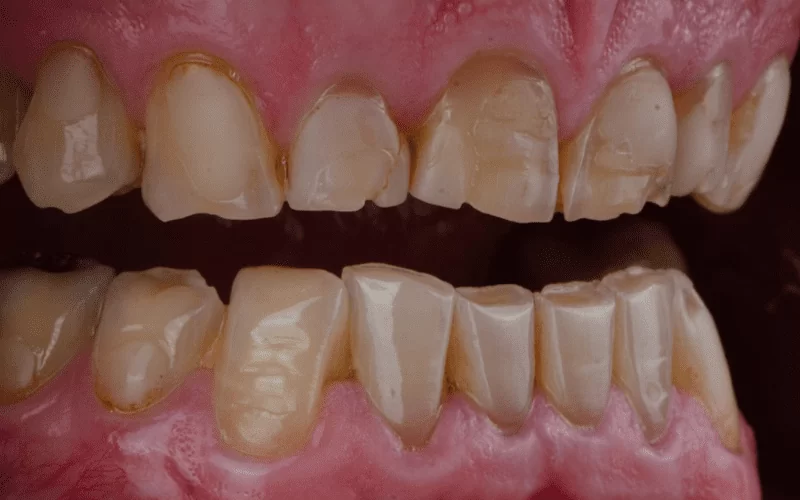

Повышенная износ зубов представляет собой патологический процесс, при котором верхний слой коронки зуба постепенно истирается, что приводит к уменьшению его высоты. В результате такого процесса повышается чувствительность зубной эмали и изменяется форма зубов, что приводит к проблемам с прикусом. Зубы начинают неправильно прилегать друг к другу.

Обычно это явление наблюдается на отдельных зубах, но в особенно тяжелых случаях может затрагивать все зубы. В настоящее время, по статистике, износ зубов встречается у 12% людей. Чаще всего мужчины обращаются к врачу с этой проблемой, так как страдают от неправильного образа жизни.

Эти изменения считаются нормальными и не должны вызывать серьезного дискомфорта у пациентов. В нормальных условиях форма коронки сохраняется, но внешний вид зуба может измениться при патологическом истирании.

При второй степени изменения становятся более заметными визуально, и зубы могут быть чувствительными к кислотам и температуре.